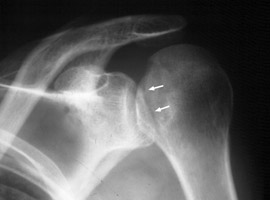

Posterior shoulder dislocation

Trough line is seen with posterior shoulder dislocation. When the humeral head is forced posteriorly in internal rotation, the anterior aspect of the humeral head is driven against the posterior glenoid rim. With sufficient force, the head will sustain a compression fracture. In many cases of posterior dislocation of the shoulder, two parallel lines of cortical bone can be seen. The outer (more medial) cortical line represent the medial cortex of the humeral head, while the other line represents the margin of a "trough" like impaction fracture.

bulletCisternino SJ, Rogers LF, Stufflebam BC, Kruglik GD: The trough line: a radiographic sign of posterior shoulder dislocation. AJR Am J Roentgenol 1978 May;130(5):951-4.          [See related articles]